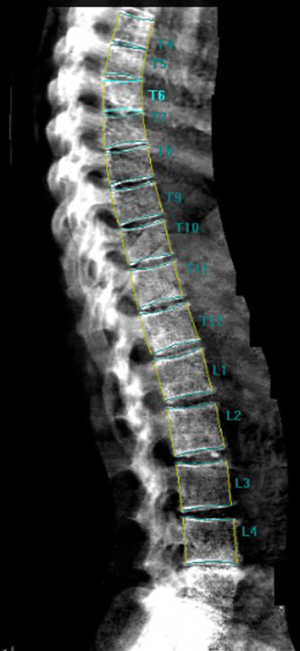

As discussed, above the increased fracture risk represents the main clinical outcome of osteoporosis. In particular, VFs represent the hallmark of osteoporosis, accounting with a prevalence of about 35% to 50% among women over 50 years of age (194). VFs frequently occur in absence of a major trauma and are often asymptomatic (195,196). Despite this, the occurrence of a VF is very important in the management of osteoporotic patients since it results in an increase in the risk of experiencing a new incident VF and other fragility fractures. Women with a pre-existing VF suffer a 4- to 5-fold increase risk of sustaining a new incident VF; this risk increases with the number of prevalent fractures at the baseline and was proved to be BMD-independent (194,197). Conventional radiography and DXA represent the techniques of choice for VFs detection (198-200). Radiologic methods for the identification and the scoring of VFs include quantitative morphometry (QM), the visual semiquantitative (SQ) method and the “algorithm-based qualitative” (ABQ) method (8). QM was introduced in order to obtain an objective and reproducible evaluation of vertebral deformities based on the measurement of vertebral body heights. QM may be performed on conventional lateral spinal radiographs or on lateral spine views acquired by DXA; the densitometric approach is commonly termed as vertebral fracture assessment (VFA) (Figure 5) (201). Typically, the center of the superior and the inferior end plates and the corner points of each vertebra from T4 to L4 are identified and then these six points are used to calculate the anterior, the middle and the posterior heights (Ha, Hm and Hp, respectively) of each vertebra and the three height ratios (Ha/Hp for wedge fracture; Hm/Hp for biconcavity fractures; ratio between Hp of adjacent vertebrae for compression fractures) (Figure 6) (38). Today, the six points placement is performed automatically with the use of a dedicated computer-assisted system to avoid inter observer variability, but manual corrections are possible at any time during the post processing of the digital images (202). Point placement may be challenging due to normal variation in the shape of vertebral bodies and projection variations; moreover, QM does not allow to distinguish between real VFs and vertebral deformities (e.g., Scheuermann’s disease, Schmorl’s node, Cupid’s bow deformity, etc.) (38,203). Unfortunately, at the current state of investigation, there is no gold standard for the definition of VFs and the exact degree of deformity that constitutes a fracture is still a matter of debate (203,204). In clinical trials, prevalent VFs are typically defined as a reduction of 3 SD or more (below the normative reference values for that particular vertebra) in any of the ratios of anterior, middle and posterior heights. In serial radiographs an incident fracture (i.e., a new VF) is defined both as an absolute change in vertebral height of at least 4 mm or as a percentage of reduction (15% or 20% reduction, depending on different studies) in the anterior, middle, or posterior heights from the baseline measurements (203,205).

The predominant approach for diagnosis of VFs is represented by the visual SQ method proposed by Genant et al. (206). On lateral spine images, VFs are identified on the basis of the apparent degree of vertebral height loss (anterior, middle and/or posterior height) and/or projected area reduction estimated by visual inspection, without direct measurements (204,206). Vertebrae from T4 to L4 are graded as normal/not fractured (grade 0), mildly deformed (grade 1: 20–25% reduction in height; 10–20% reduction of projected vertebral area), moderately deformed (grade 2: 25–40% reduction in height and 20–40% reduction of projected vertebral area) and severely deformed (grade 3: >40% reduction in any height and projected vertebral area) (206). However over time, the area reduction requirement was excluded from the examination (205). Since a linear relationship exists between the number and severity of prevalent VFs and the risk of future VFs, a spinal deformity index (SDI) can be derived from this scoring system, resulting from the sum of all grades assigned to the vertebrae divided by the number of evaluated vertebrae (38,197). The SQ method has been extensively validated and according to the ISCD official positions it represents the technique of choice for diagnosing VFs with VFA (207,208,209). Its major strength relies on the visual approach that, in experienced hands, allows to discriminate fractures from non-fracture deformities (208,209). However, a critical point of this method is represented by the accurate estimation of vertebral height reduction, especially when the degree of this reduction is close to the thresholds of the grading system (204). In light of the above issues, we believe that an integrated approach may be preferable for defining and reporting VFs. In particular, the use of QM should be encouraged to objectively graduate VFs, previously identified by the SQ method, in epidemiological studies and follow up evaluations (202).